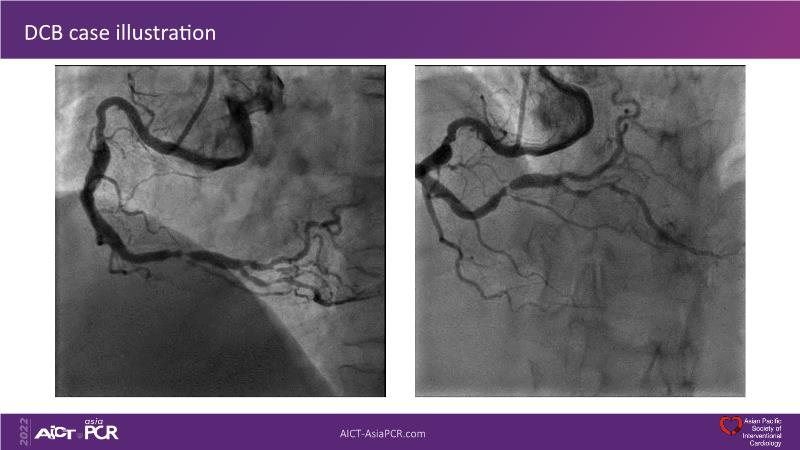

Sirolimus coated balloon: expanding the scope of coronary artery disease treatment

Consult this session to understand the technology and scientific evidence of the novel sirolimus drug-coated balloon, to learn its utility for PCI in a variety of lesion and patient subsets and to understand the evidence and outcomes in real-world patients.

- To learn the utility of the DCB for PCI in a variety of lesion and patient subsets